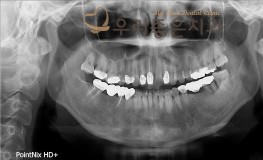

우리좋은치과 치주질환으로 인한 골소실 → 임플란트 보철 치료 (백** 2019.05..

No.346

임플란트

2019-11-25

1545